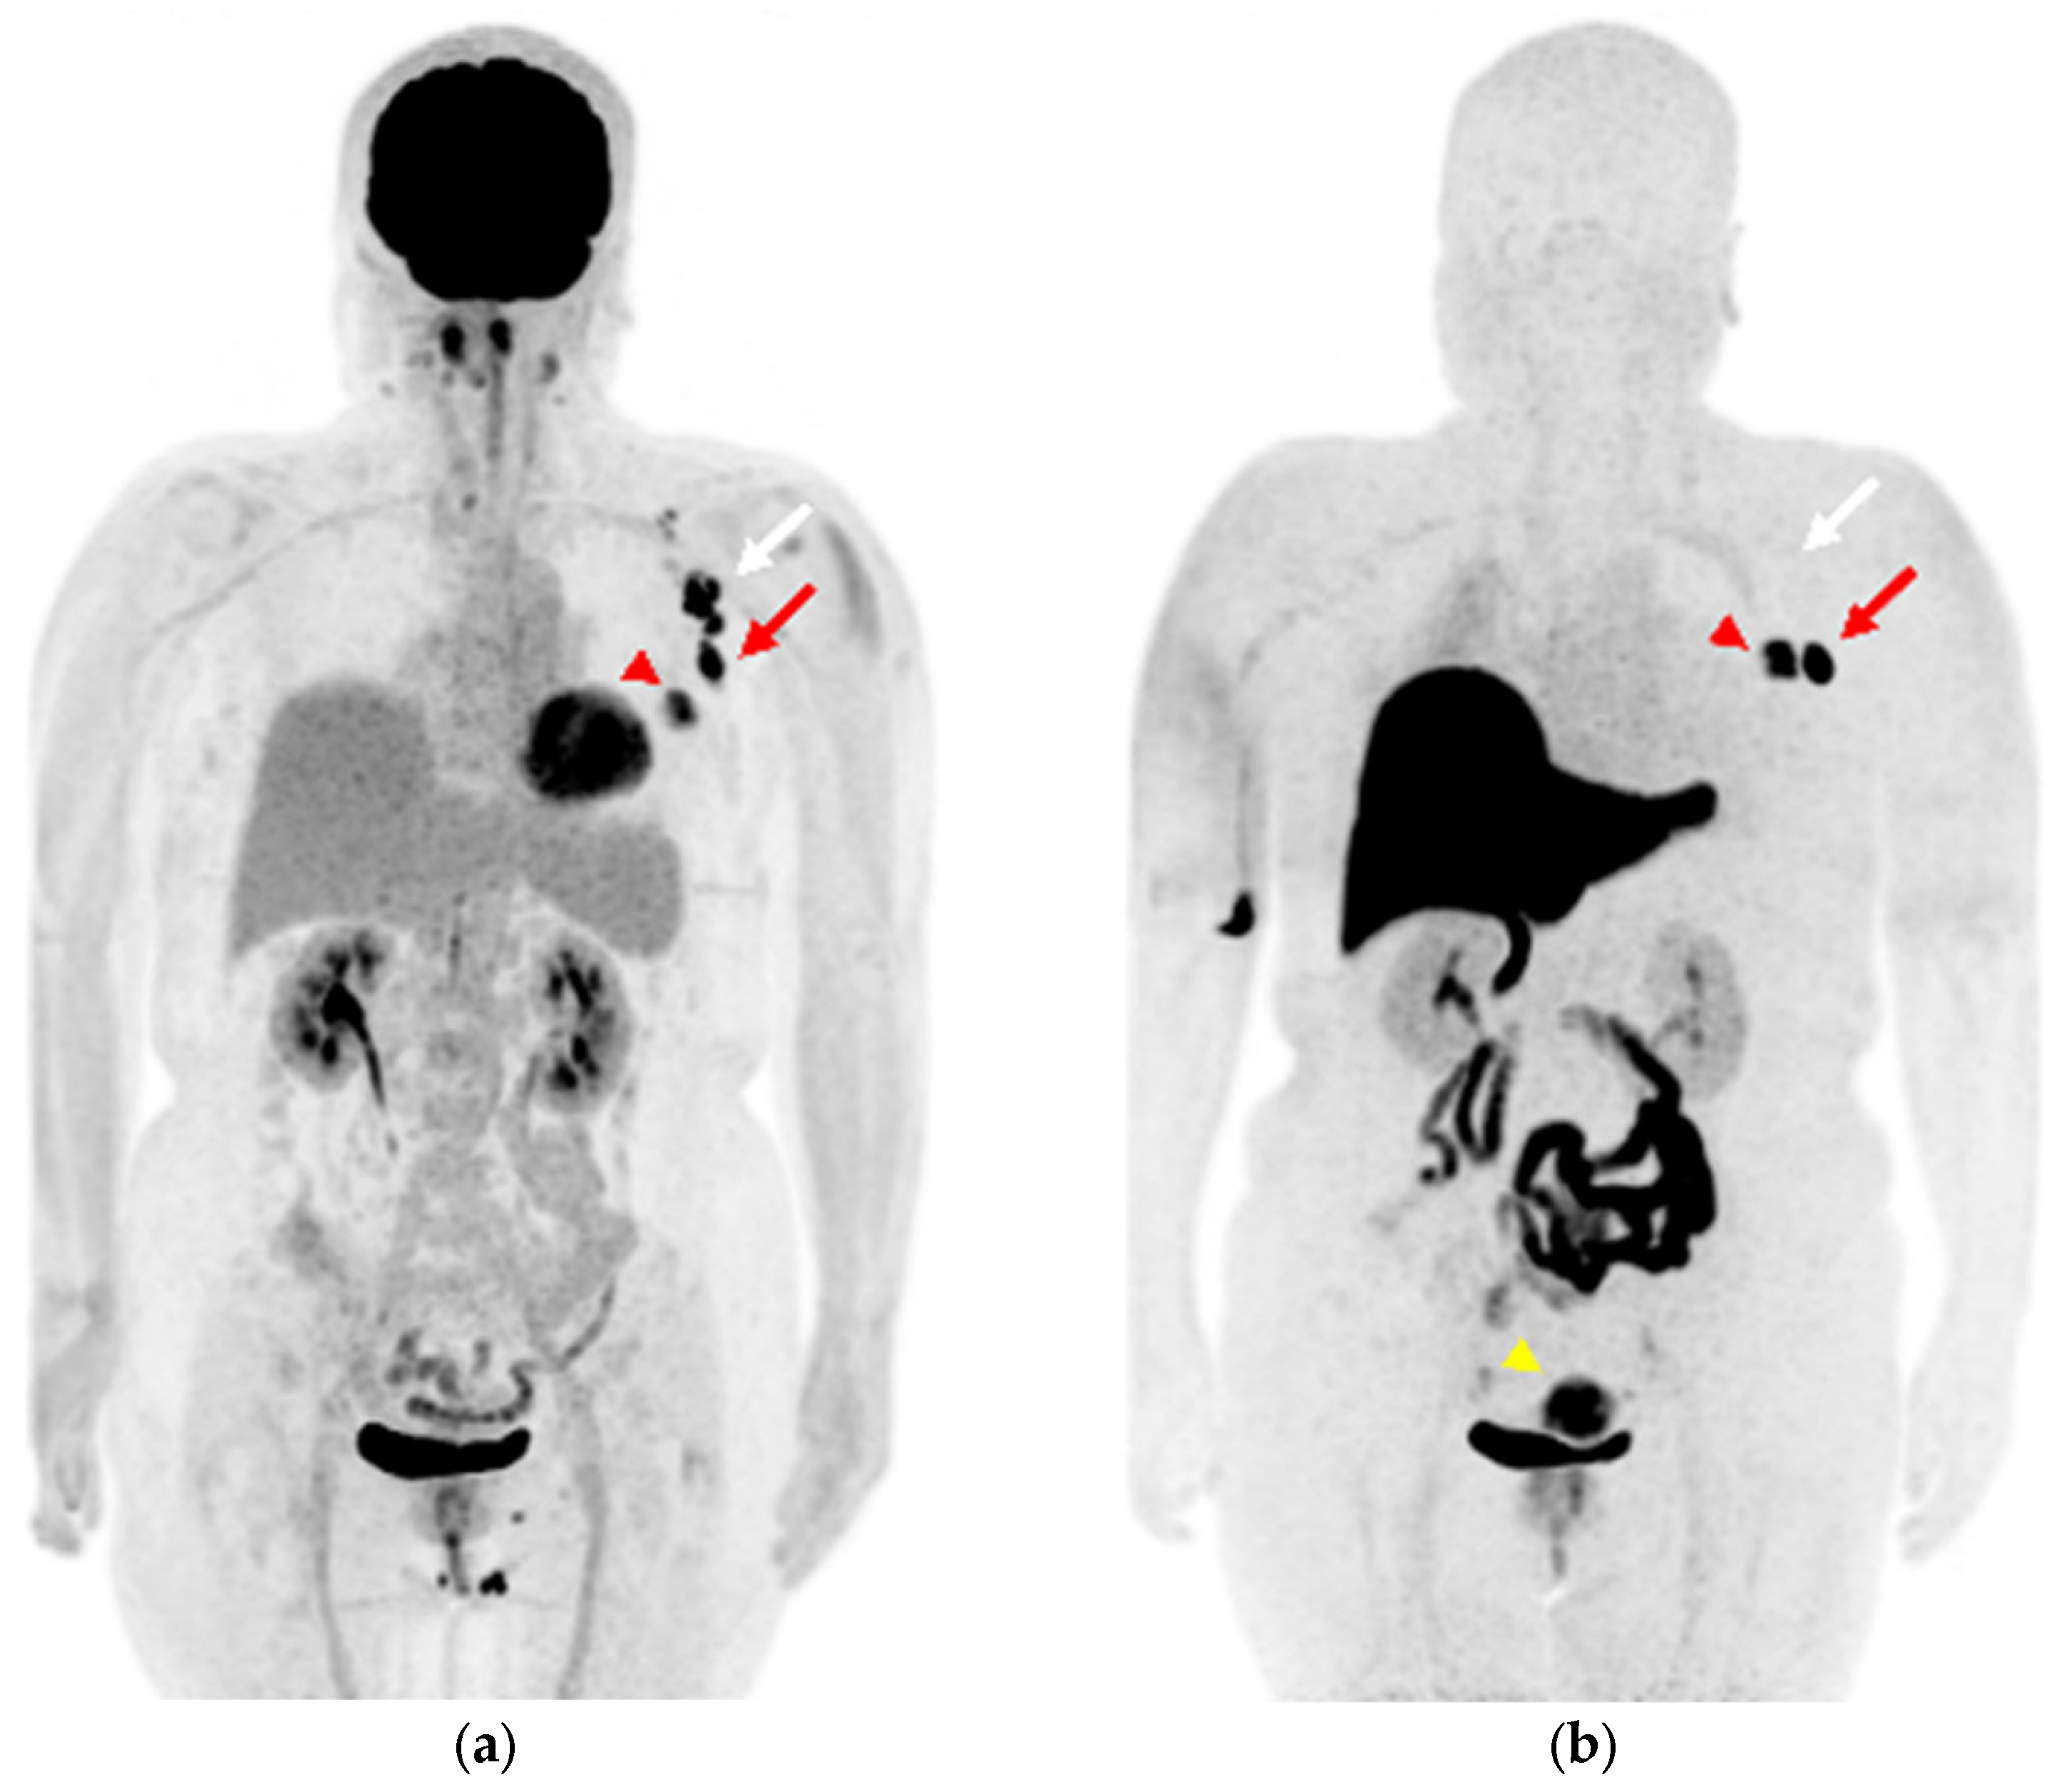

A 59-year-old woman was diagnosed with ER-positive left breast cancer on histopathological examination, including hematoxylin and eosin (H&E) staining and immunohistochemistry (IHC) (ER 90%, PgR 30%, HER2 score1, MIB-1 index 30%) She underwent [18F]FDG PET/magnetic resonance imaging (MRI) for preoperative staging. The primary lesion in the breast, as well as multiple level I and II left axillary lymph nodes, showed significant FDG uptake (Figure 1a and Figure 2a–c). The patient had received the COVID-19 vaccine in the upper left arm 3 days prior to examination, and there was marginal FDG accumulation in the left deltoid muscle, suggesting inflammatory changes due to vaccine administration. Nineteen days after [18F]FDG PET/MRI, [18F]FES PET/MRI was performed again to assess ER expression in the lymph nodes (Figure 1b and Figure 2d,e). The largest axillary lymph node showed considerable FES uptake (Figure 1b and Figure 2d, red arrow), a finding consistent with lymph node metastasis; however, the other nodes with FDG accumulation did not show remarkable FES uptake (Figure 1b and Figure 2e,f, white arrows), indicating that the FDG uptake was due to inflammatory changes associated with vaccine administration. Uterine leiomyoma, another estrogen-dependent tumor, showed intense [18F]FES uptake in the pelvis (Figure 1b, yellow arrowhead).

Figure 1.

(a) Maximum-intensity projection (MIP) of [18F]FDG positron emission tomography (PET) image; (b) MIP image of [18F]FES PET. ((a), red arrowhead) The left breast cancer shows intense [18F]FDG uptake and ((b), red arrowhead) [18F]FES uptake. ((a), arrows) The ipsilateral axillary lymph nodes show intense [18F]FDG uptake, ((b), arrows) while [18F]FES PET is hyperintense only in the lesion with the red arrow. ((b), yellow arrowhead) Uterine leiomyoma shows intense [18F]FES uptake in the pelvis.